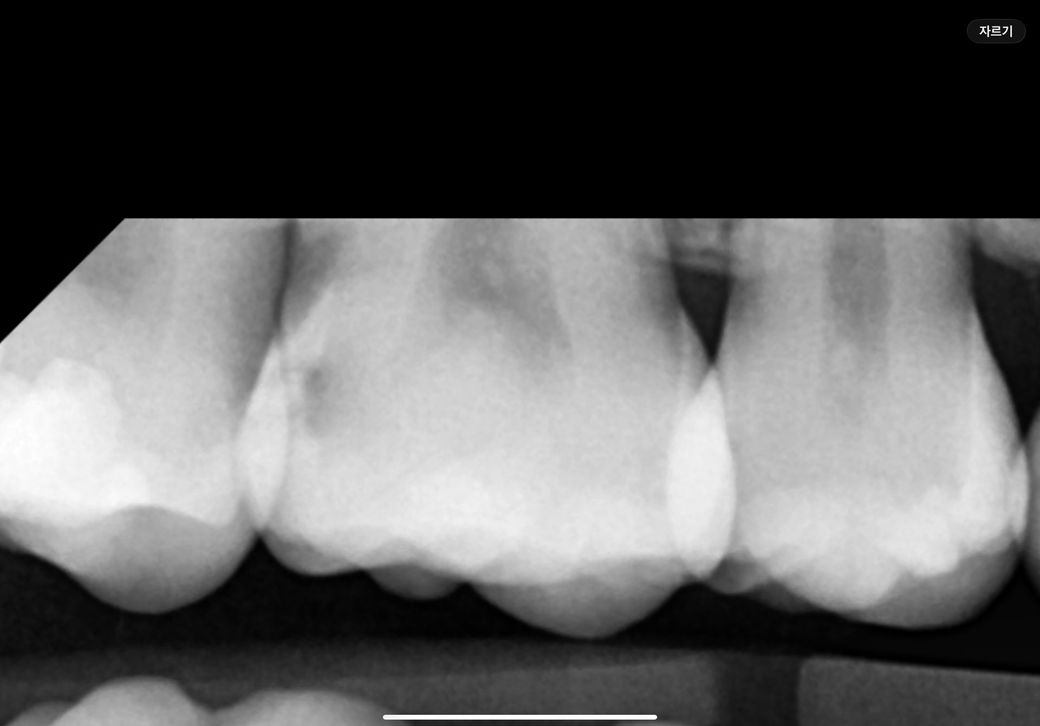

제 이빨이 인레이로 치료가 필요한 상태인가요?

오늘 치과에 갔는데 인접면 충치에 하필 신경과 가까이 있는 충치라 레진 인레이+신경단열? 하는거 하나 깔아야 한다고 하셨습니다. 일단 충치라는 말에 겁에 질려서 받기는 했으나 꼭 필요한 치료였을까요? 레진으로는 힘든 치아상태 인가요?

1. 엑스레이 사진상으론 인접면 충치가 맞고요

2. 어차피 인접면 충치는 옆으로 접근이 불가능해서 위에서부터 뚫고 들어갑니다 그렇게 되면 레진으로는 옆 치아와 정밀한 컨택을 얻기 어렵고요. 그거 해주는 치과도 있는데 인레이 값 이상 받을 겁니다